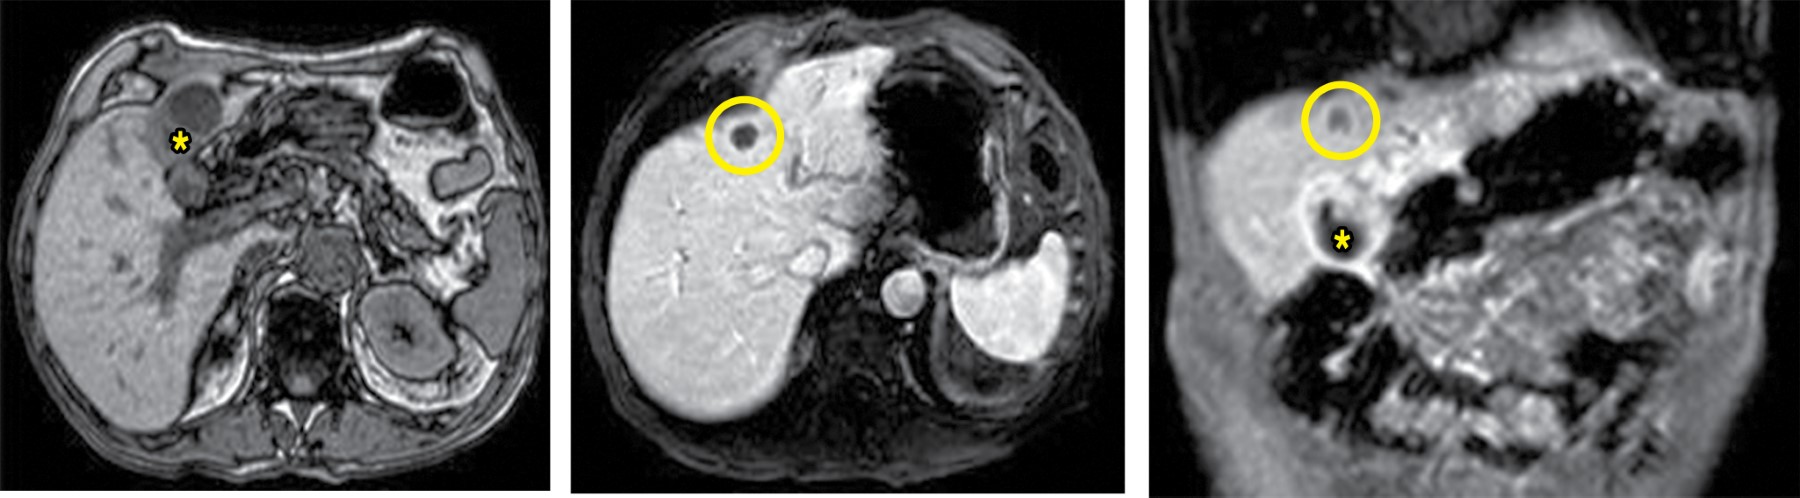

Caso 5. Hombre de 75 años, intervenido 30 años antes por úlcera gástrica. Consultó por pérdida ponderal y tumoración sobre el extremo craneal de la laparotomía media, dolorosa y no reductible a la exploración. La TC objetivó una colección subcutánea de 10 × 6 cm en continuación transparietal con una vesícula biliar de contornos irregulares y paredes engrosadas que sugería colecistitis evolucionada. Además, informó de una lesión focal de 9 mm en el segmento IVb compatible en el contexto clínico con un absceso hepático.

Se realizó tratamiento AB y DP. La col-RM posterior objetivó un engrosamiento heterogéneo de la pared vesicular, adenopatías en el hilio hepático y la lesión focal en el segmento hepático IVb previamente descrita (Figura 4). Se realizó biopsia de la lesión hepática, con resultado inmunohistoquímico de adenocarcinoma metastásico de origen biliopancreático. El estudio de extensión mediante PET-TAC mostró captación patológica en la vesícula, el hilio hepático, la lesión del segmento IVb y un nódulo en el pulmón derecho. Se indicó quimioterapia paliativa y colocación de una endoprótesis biliar, con buena evolución inmediata al respecto de la resolución del cuadro séptico y la FCC. Falleció transcurridos 14 meses desde el diagnóstico de la neoplasia de vesícula.